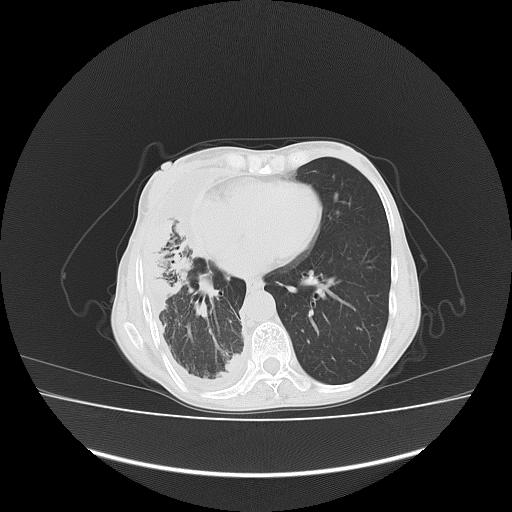

可见多发肺内病灶,且胸膜病灶较多有圆球状而非丘状,多考虑胸膜转移瘤伴胸腔积液,右侧胸廓缩小固定,且部分病灶呈丘状,尚不除外恶性胸膜间皮瘤伴肺内转移

右侧胸膜增厚,局部呈结节状增厚,右侧胸腔少量积液。双肺未见确切肿块影。纵隔未见淋巴结肿大。气管、支气管通畅。考虑右侧胸膜间皮瘤(恶性?)可能性大。不除外癌性胸膜炎。

恶性胸膜间皮瘤伴肺内转移可能性大;或胸膜、肺内均为转移瘤,左肺下叶亦见多发小结节影。

右侧胸廓塌陷,右侧胸膜广泛增厚并见多发胸膜结节,右侧少量胸腔积液并包裹。

右侧广泛胸膜增厚,局部呈结节状增厚,右侧胸腔少量积液。双肺未见确切肿块影。纵隔未见淋巴结肿大。气管、支气管通畅。考虑右侧胸膜间皮瘤(恶性?)可能性大。支持!

右侧胸膜转移瘤,原发灶可能就在在右肺,另外建议检查右侧乳腺.

右胸腔结节均考虑来自胸膜(部分来源于叶裂),考虑胸膜间皮瘤或转移瘤.